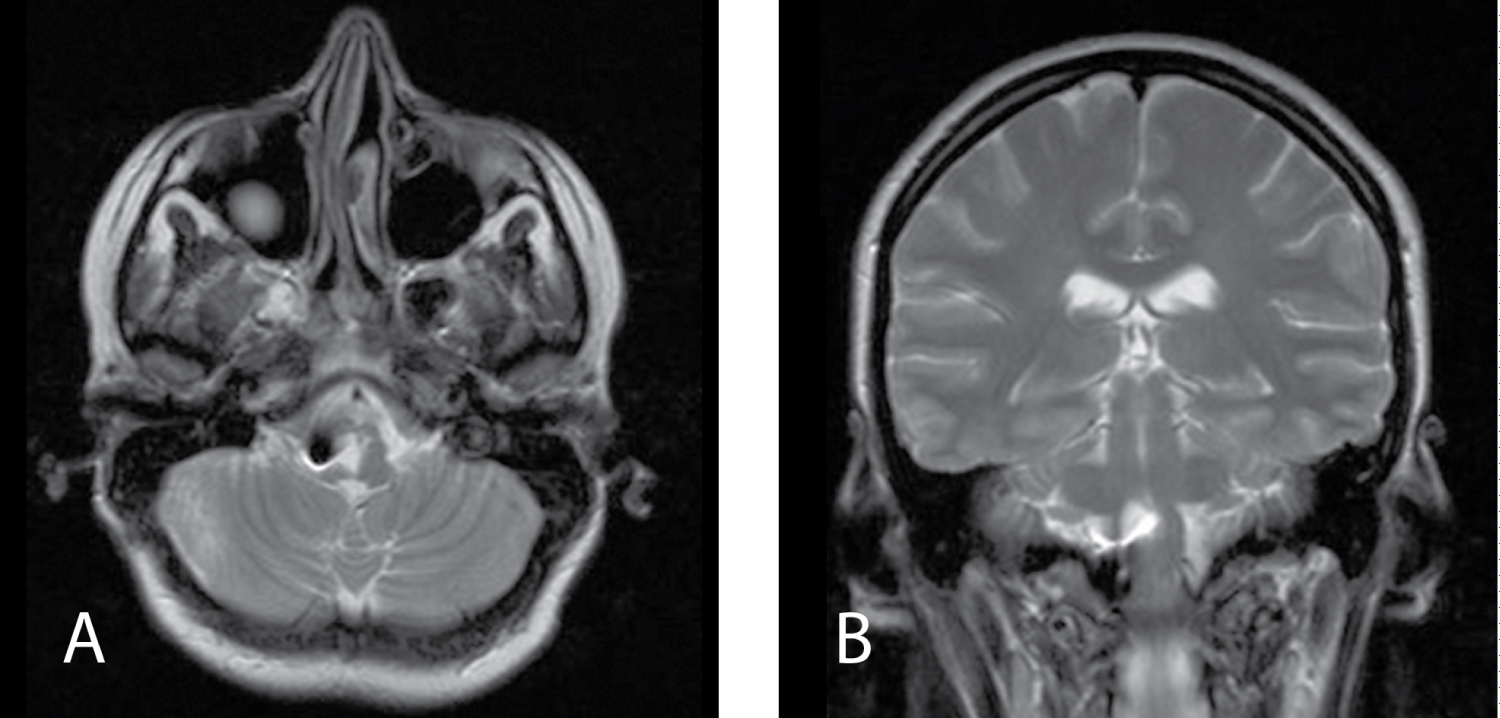

Two months after operation patient presented with mild dysphagia and dysphonia, vertigo, spontaneous nystagmus, imbalance and numbness of the left side of body and right limb including face and mild left-sided hemiparesis before MRI was planned.

Result of MRI revealed reccurence of the cyst. As it was before the lesion had well-defined, heterogeneously hyper- and isointense on T1-weighted images, demonstrated no solid enhancing components but homogeneously hyperintense on T2-weighted images now. Sites of hyperintesity were less pronounced than on MRI before the first surgery (Figure 2).

Figure 2: MRI 2 months after first surgery. A) MRI Т1 axial view; B) MRI Т2 frontal view. View Figure 2

MRI examination is a method of choice in the diagnostic algorithm of NC but its characteristics can be variable. It shows well-demarcated lesions iso- or tightly hypointense in T1 and hyperintense in T2-weighted sequences and FLAIR [5,6,8,17,18]. NCs usually demonstrate no contrast enhancement but Prasad, et al. reported mild posterior rim enhancement that can be explained by chronic inflammatory changes due to repeated cyst rupture in their view [19]. In our case MRI characteristics were not typical. Before the first the surgery lesion was heterogeneously hyperintense on T1-weighted imagesand homogeneously hypointense on T2-weighted images (Figure 1). Before second surgery MRI characteristics have changed. It was hyperintense in T2 and sites of hyperintesity in T1 were less pronounced than before the first surgery (Figure 2) that is most likely for NCs. Such change of signal can be explained by high concentration in liquid cyst cavity. It led to heterogeneously hyperintense on T1-weighted images and homogeneously hypointense on T2-weighted images before first operation.